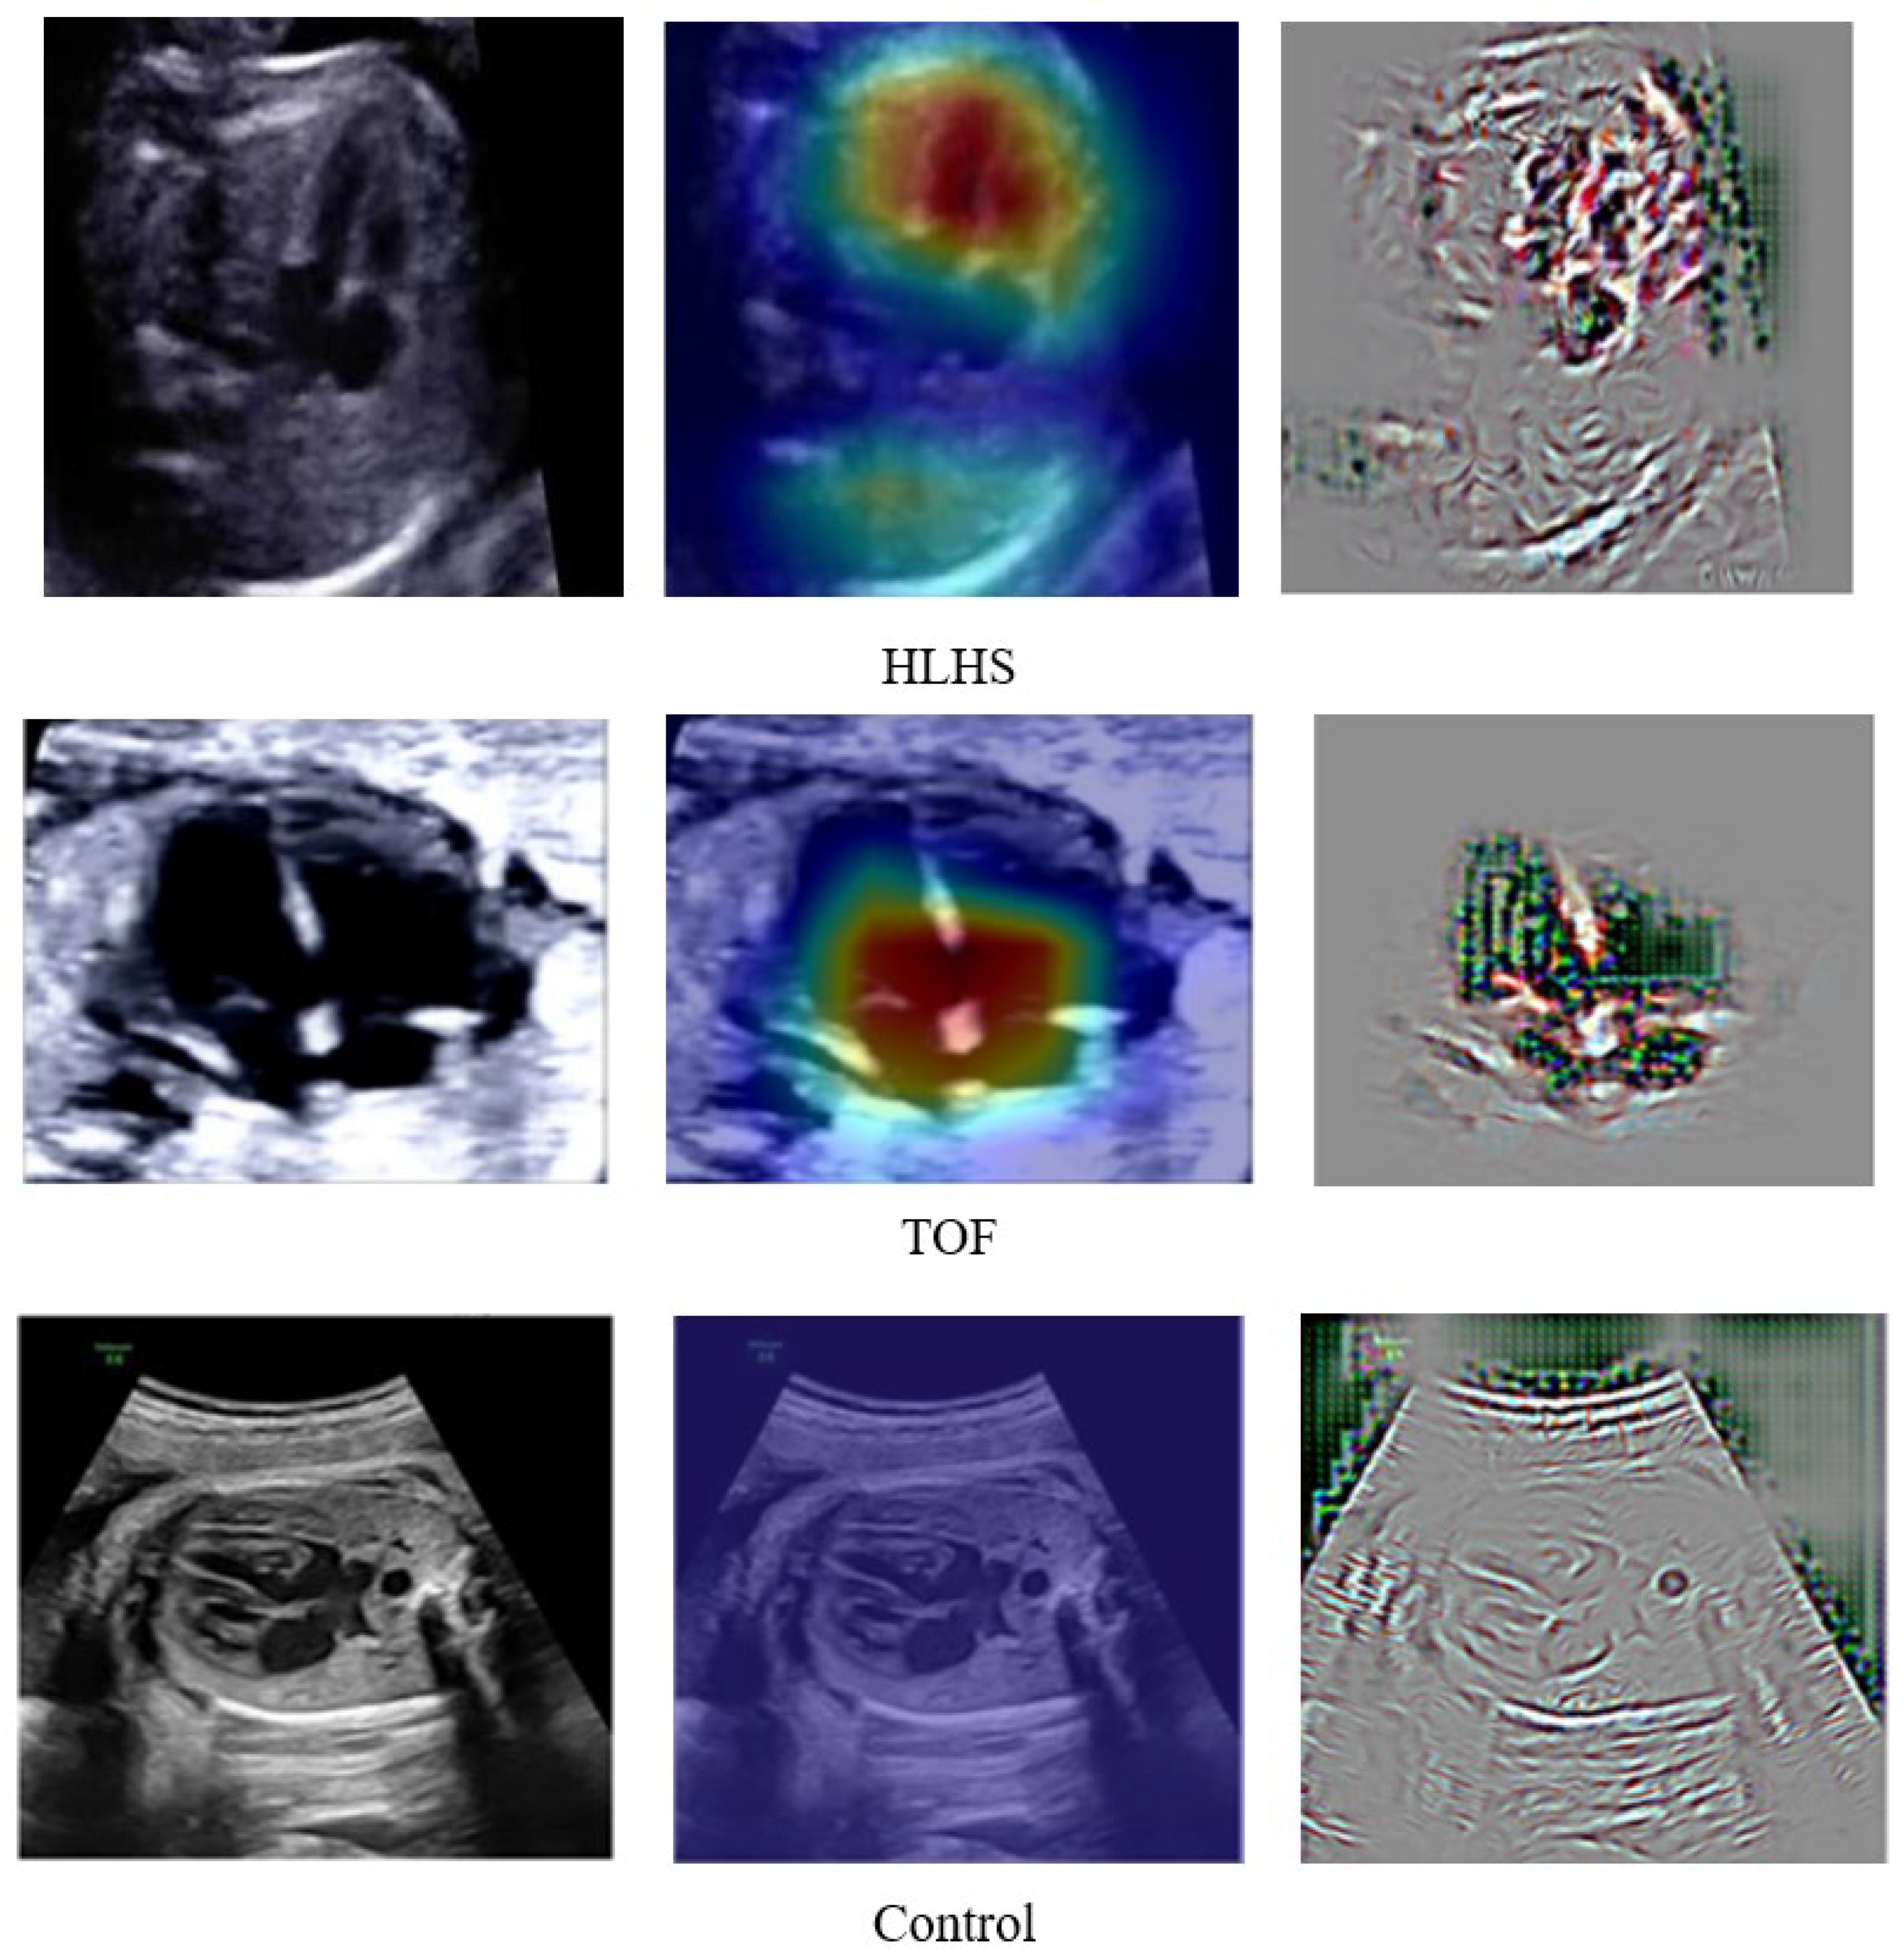

To explain the results of DenseNet201 classification so that they can be easily understood medically, we created a visualized image output after the classification process. A combination of guided backpropagation (Guided–BP) and gradient class activation mapping (Grad–CAM) was combined to describe abnormal pixels from US images as CHDs. Combining Guided–BP and Grad–CAM allowed us to generate sharp attributions. Class-discriminative visualization enables expert fetal cardiologists to understand where models are predicted. It can be used for any CNN-based model. A good explainable model should highlight fine-grained details in the image to visually explain why the model predicted a class. Such results can improve expert fetal cardiologists understanding from a medical point of view. Figure 8 depicts the raw image, Grad–CAM, and a combination of Guided–BP and Grad–CAM visualization. There was an excellent localization process for most of the images used in our experiment. Such visualizations can be used to inform downstream model enhancements.

Figure 8.

DenseNet201 Classification Result Explained by Guided–BP and Grad–CAM.